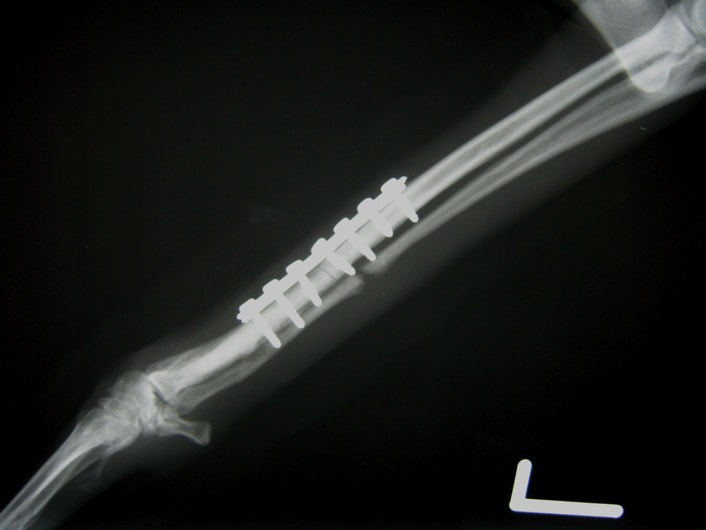

トイプードル 右遠位橈尺骨短斜骨折のALPSによる内固定

Locking Compression Plate

LCPは、スクリュー(ネジ)とプレート(金属の板)をロックする特殊な構造により骨折部位を固定する新しい世代のプレートシステムです。ひとつのホールでロッキングスクリューとスタンダードスクリューの使用を選択できるユニークな構造をしているため、骨折断端間の圧迫を目的とした従来型プレート固定法に加え、高い角度安定性を有するロッキングスクリューを用いた固定法の選択が可能です。従来のプレートシステムでは困難だった部分の骨折や癒合不全の症例に高い治療効果をもたらします。

当院ではAdvanced Locking plate system(ALPS)と、Locking compression plate system(LCPS)という骨接合法で骨折症例の治療を行っています。